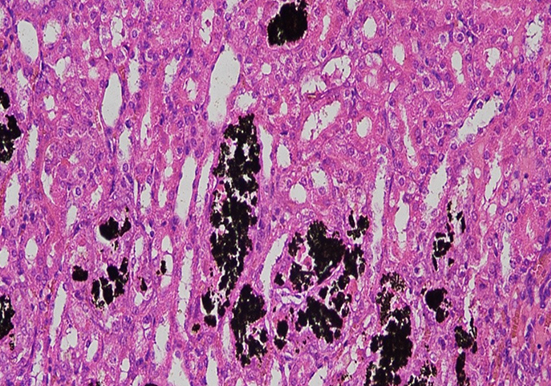

嗜酸性粒细胞染色

以下是关于嗜酸性粒细胞染色的相关内容:染色方法瑞氏染色原理:瑞氏染料由酸性染料伊红(E-)和碱性染料亚甲蓝(M+)组成。既有物理的吸附作用,又有化学的亲和作用。血红···

抗酸染色

以下是关于抗酸染色的详细介绍:基本原理细胞壁结构特殊:分枝杆菌的细胞壁含有大量的脂质,尤其是分枝菌酸,形成致密的蜡样包膜。这种包膜具有疏水性,普通染色剂的极性分···